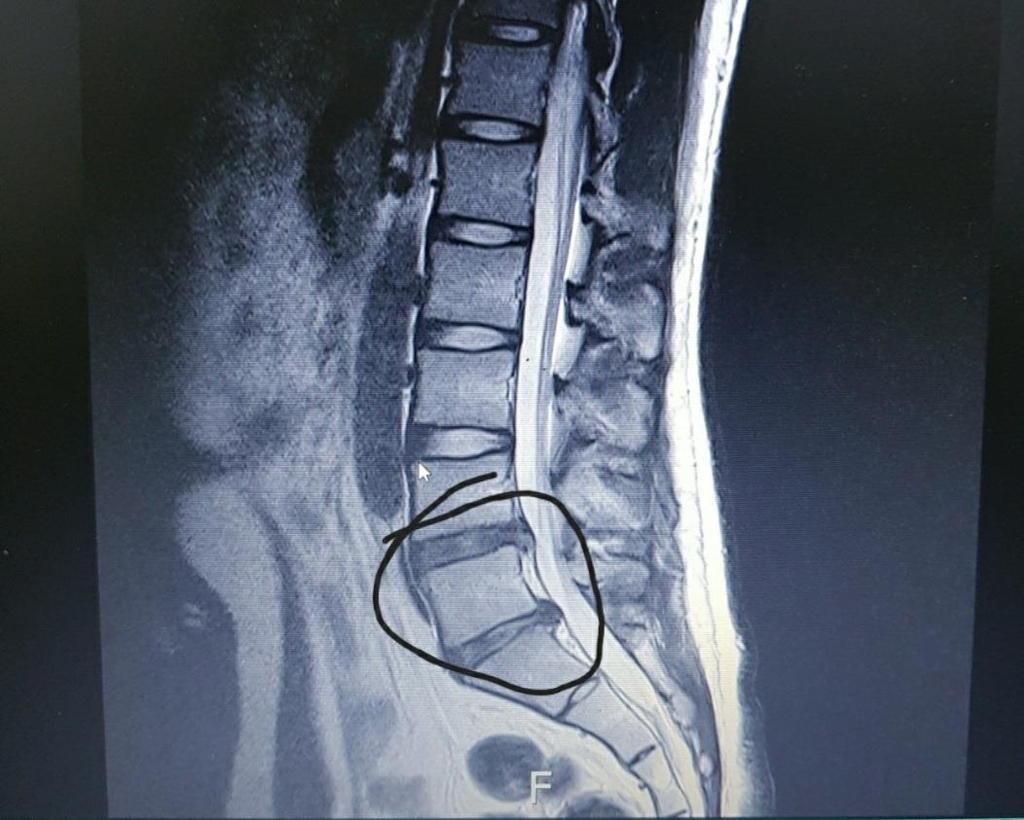

허리디스크는 현대인에게 매우 흔한 문제이며, 이를 통해 다양한 증상이 나타날 수 있습니다. 허리디스크, 즉 추간판 탈출증은 척추 디스크가 돌출되거나 파열되어 신경을 압박하게 되는 상황을 말합니다. 이로 인해 통증과 불편함이 발생하며, 일상생활에 큰 지장을 줄 수 있습니다.

허리디스크는 다양한 증상을 동반하며, 개인마다 증상의 강도와 양상이 다를 수 있습니다. 일반적으로 허리 통증은 가장 흔하게 나타나는 증상 중 하나입니다.